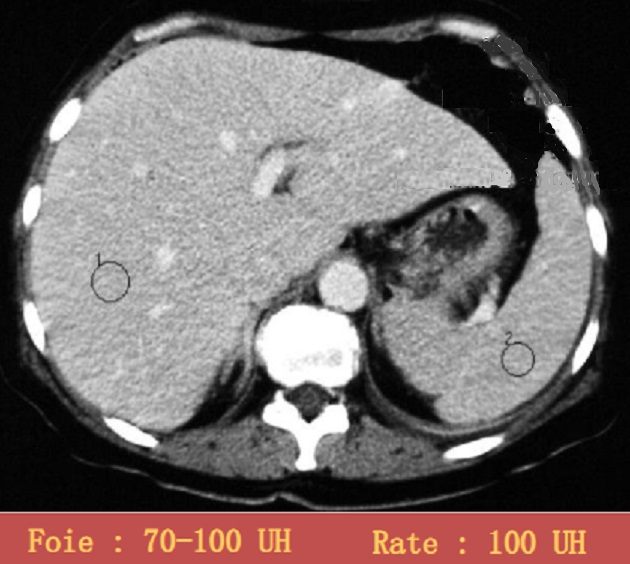

Image radiologique TDM plus + de

contrast intraveineuse. La parenchyme de la rate au debut

rehausse hyperdensite non homogene et puis homogene

avec densite a egale du foie ( 100UI ) . Image

radiologique TDM avec contrast intraveineuse en

coupe axial , phase tardive |